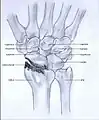

Post-traumatic osteoarthritis can be classified into four stages.[1][6] These stages are similar between SLAC and SNAC wrists. Each stage has a different treatment.

- Stage I: the osteoarthritis is only localized in the distal scaphoid and radial styloid.

- Stage II: the osteoarthritis is localized in the entire radioscaphoid joint.

- Stage III: the osteoarthritis is localized in the entire radioscaphoid joint with involvement of the capitolunate joint.

- Stage IV: the osteoarthritis is located in the entire radiocarpal joint and in the intercarpal joints. It also may involve the distal radio-ulnar joint (DRUJ).